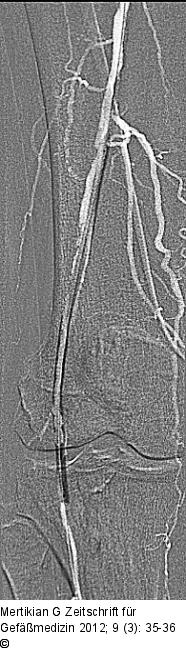

Abbildung 5: Re-entry-Katheter PTA mit 4/150 mm-Ballonkatheter |